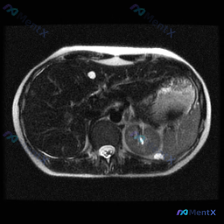

先看病例的影像客观发现

- 肝脏:右叶可见一处类圆形高信号影,边界清晰锐利,信号均匀;

- 脾脏:外后缘可见一处类圆形高信号影,边界清晰,信号均匀;

- 左肾:肾实质内可见一处边界尚清、形态不规则的低信号区域,内部可见高信号裂隙样改变;

- 其他:腹腔内未见明显游离液体,胃腔内有内容物信号,当前层面椎体及周围组织未见明显肿块。